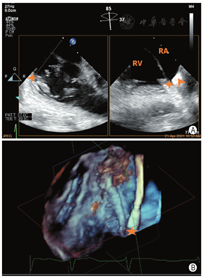

手术过程:患者于复合手术室取平卧位,常规消毒铺巾,静脉复合麻醉后。①穿刺左侧桡动脉监测血压,穿刺右侧股动脉/股静脉分别置入6F/6F鞘管,右冠状动脉造影正常,然后于右冠状动脉内放置冠状动脉导丝(ASAHI SION PTCA Guide wire,0.014″×180 cm)以标记右冠状动脉与三尖瓣后瓣环的空间位置关系。②穿刺右侧颈内静脉,预置1把ProGlide后,穿刺置入9F鞘管,然后进入Amplatz Superstiff (Amplatz Superstiff J Tip Guider wir,0.035′×260 cm)导丝,并在二维(2D)TEE食管中段上下腔切面监测下将导丝置入下腔静脉入口处(图3),退出9F鞘管,将18F K-clip可调弯鞘(下称大鞘)在2DTEE和(或)三维(3D)TEE食管中段上下腔切面监测下缓慢推进至右房中下部(图4),并固定于无菌床头固定器上。③沿大鞘进入K-Clip可调弯输送系统至大鞘末端并后撤大鞘4~5 cm,在2DTEE、3DTEE及DSA引导下调整K-Clip输送系统至三尖瓣瓣环前后叶交界处(图5),并拧入固定螺丝,张开K-Clip夹合臂并调整夹合臂方向与三尖瓣瓣环切线平行,进行夹合(图6,图7)。④夹合术后即刻彩色多普勒显示TR程度由5+(极重度)减少至2+(中度)(图8),连续多普勒记录三尖瓣平均跨瓣压差为1 mmHg,3DTEE描记三尖瓣瓣口面积由术前8.50 cm2减少至5.33 cm2(图9),2DTEE检查无瓣叶损伤及心包积液,冠状动脉造影提示RCA中远端50%左右压迫狭窄,前向血流TIMI 3级,此时患者血压为116/70mmHg,心率为70次/min,基本平稳,逐释放K-Clip夹合器,撤出输送系统并退出大鞘,ProGlide血管缝合右侧颈内静脉,手术完成。